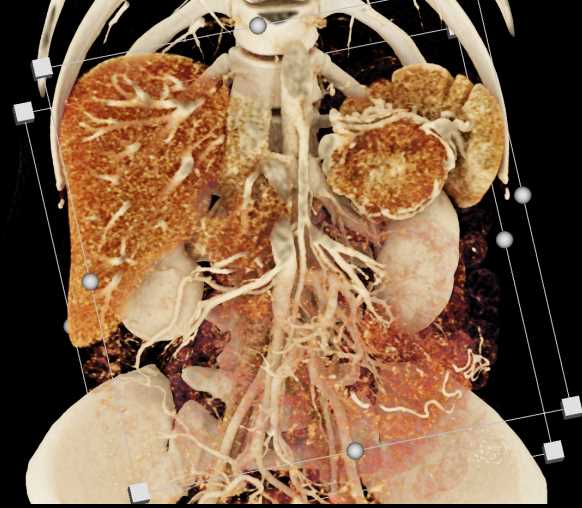

Neuroendocrine Tumor Pancreas